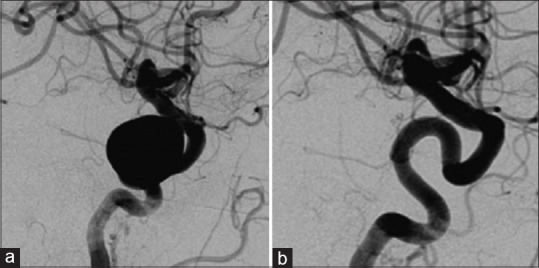

复杂的颅内动脉瘤给神经介入领域带来了巨大挑战,需要精心策划和实施。本文强调了麻醉师在这些手术中扮演的关键角色,包括患者评估、麻醉计划、持续监测和维持血流动力学稳定,这些对于优化患者安全至关重要。了解这些复杂的手术及其并发症将有助于麻醉师提供最佳护理,并预见和处理潜在的相关并发症。麻醉师的职责不仅限于手术本身,还包括术后护理,确保顺利过渡到恢复阶段。在复杂颅内动脉瘤的血流分流介入手术中,成功的围手术期麻醉管理取决于对这些要素的精心安排。此外,与介入神经放射科医生和手术团队的有效沟通和合作也很重要,因为这对手术的成功有很大帮助。本文强调了在管理接受神经介入治疗的患者时,多学科团队方法的基本要求。在这一合作框架中,麻醉师的专业技能与其他团队成员的技能和知识相辅相成,为这些手术的整体成功和安全做出了贡献。通过在整个围手术期提供高水平的护理,麻醉师在提高患者预后和最大限度地降低这些复杂手术的相关风险方面发挥着举足轻重的作用。总之,使用血流分流器对复杂颅内动脉瘤进行神经介入手术的围手术期麻醉管理是一个多方面的过程,需要专业知识、沟通和协作。

Complex intracranial aneurysms pose significant challenges in the realm of neurointervention, necessitating meticulous planning and execution. This article highlights the crucial roles played by anesthetists in these procedures, including patient assessment, anesthesia planning, and continuous monitoring and maintaining hemodynamic stability, which are pivotal in optimizing patient safety. Understanding these complex procedures and their complications will aid the anesthetist in delivering optimal care and in foreseeing and managing the potential associated complications. The anesthetist's responsibility extends beyond the procedure itself to postprocedure care, ensuring a smooth transition to the recovery phase. Successful periprocedural anesthetic management in flow diverter interventions for complex intracranial aneurysms hinges on carefully orchestrating these elements. Moreover, effective communication and collaboration with the interventional neuroradiologist and the procedural team are emphasized, as they contribute significantly to procedural success. This article underscores the essential requirement for a multidisciplinary team approach when managing patients undergoing neurointerventions. In this collaborative framework, the expertise of the anesthetist harmoniously complements the skills and knowledge of other team members, contributing to the overall success and safety of these procedures. By providing a high level of care throughout the periprocedural period, anesthetists play a pivotal role in enhancing patient outcomes and minimizing the risks associated with these intricate procedures. In conclusion, the periprocedural anesthetic management of neurointervention using flow diverters for complex intracranial aneurysms is a multifaceted process that requires expertise, communication, and collaboration.